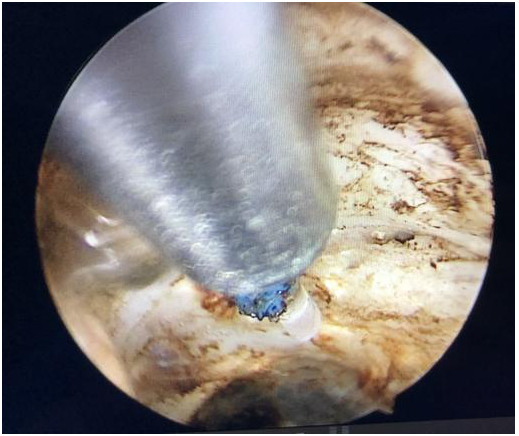

沿前列腺包膜剜除